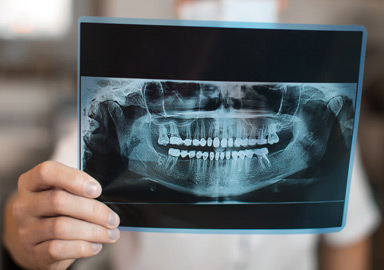

Proporciona una vista panorámica de la estructura dental y maxilofacial, ideal para evaluar el estado general de la mandíbula y los dientes.